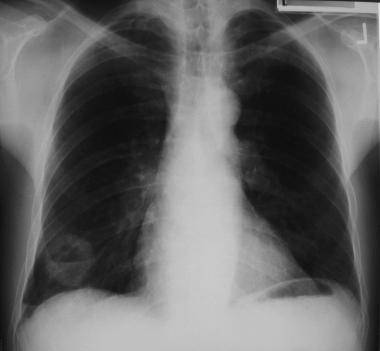

У трети пациентов наблюдаются незначительные признаки поражения органов дыхания. Особенностью туберкулеза легких является отсутствие симптомов или минимальное их проявление. В основном его выявляют при профилактических осмотрах. Основную картину туберкулеза дает рентгенография легких, но она имеет различие в зависимости от фазы и продолжительности процесса.

Почему возникают и чем опасны очаги в легких

Существует определенная разница между международно установленным понятием очаговых образований, и тем, что принято в отечественной медицине. За рубежом к ним относят уплотнения в легких размером около 3 см. Отечественная медицина ставит ограничения до 1 см, а другие образования относит к инфильтратам.

Провести аппаратным методом четкую диагностику заболевания не позволяет несовершенство оборудования. При прохождении рентгенографии легких трудно обнаружить очаговые изменения, размер которых не достигает 1 см. Интерпозиция анатомических структур делает невидимыми и более крупные образования.